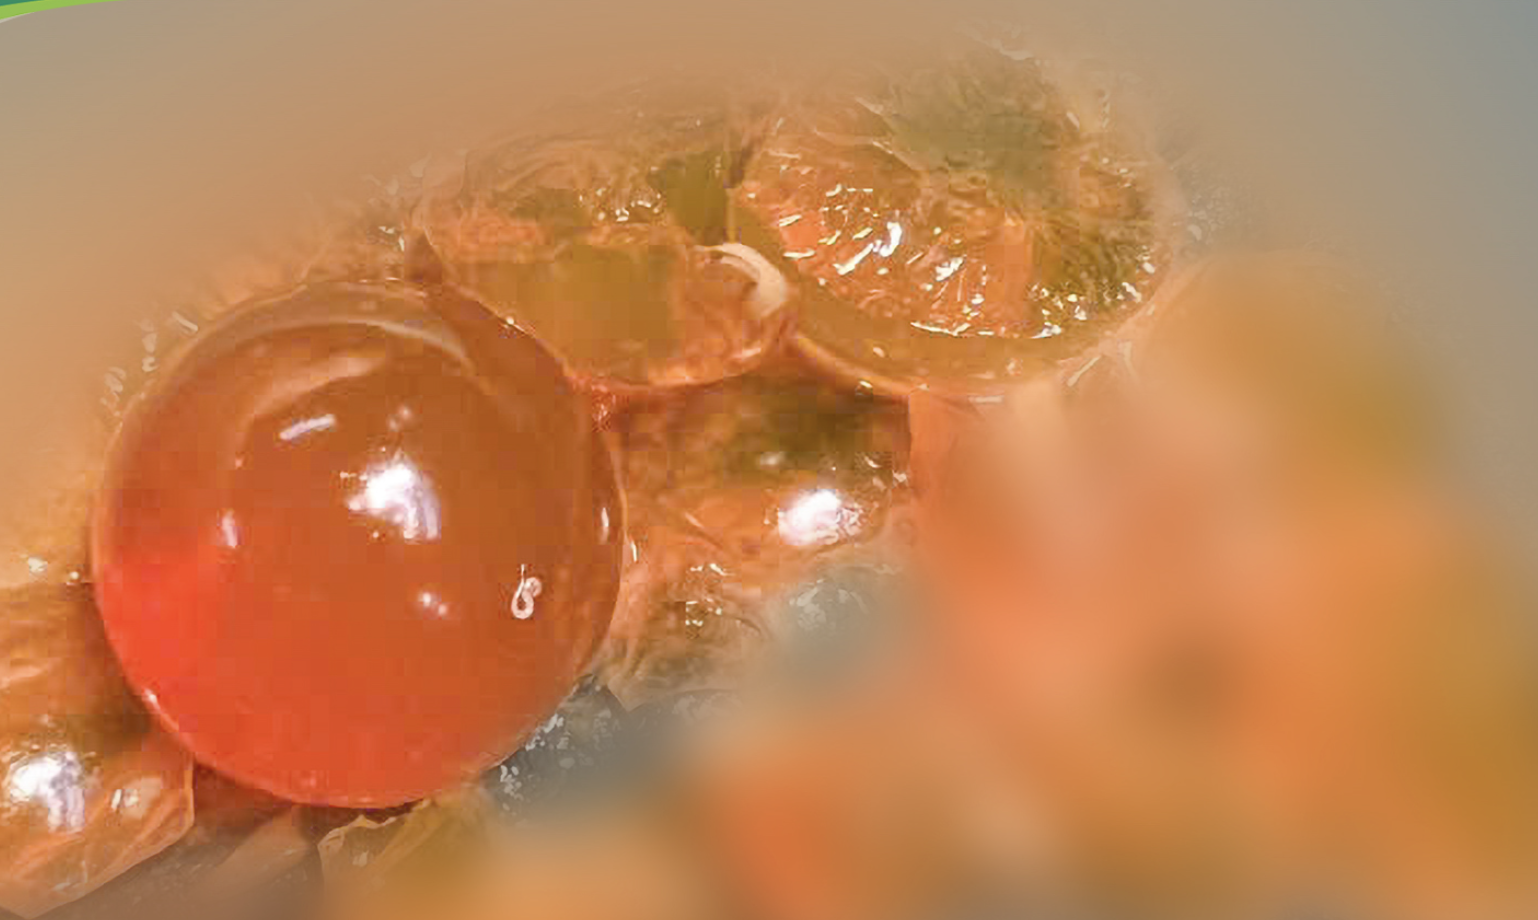

Bác sĩ Nguyễn Đức Thường, Phó trưởng khoa điều trị tích cực ngoại khoa, Bệnh viện Nhi trung ương, cho biết: “Trong quá trình phẫu thuật, các bác sĩ phẫu thuật xác định có bốn hạt nở nằm trong lòng ruột non, gây tắc hoàn toàn đường ruột.

Ê kíp đã lấy toàn bộ số hạt nở này ra ngoài. Rất may bệnh nhi được phát hiện và phẫu thuật kịp thời nên không phải cắt ruột”.

Theo các bác sĩ, hạt nở là một loại đồ chơi khá phổ biến dành cho trẻ em, có dạng những hạt nhựa nhỏ li ti, đường kính khoảng 2-5mm, với nhiều màu sắc sặc sỡ.

Khi ngâm trong nước, các hạt này có thể trương nở gấp hàng chục đến hàng trăm lần kích thước ban đầu, tạo nên hình ảnh bắt mắt, thu hút trẻ nhỏ.

Dị vật được lấy ra là những hạt nhựa nhỏ, có khả năng trương nở khi gặp nước – Ảnh: BVCC